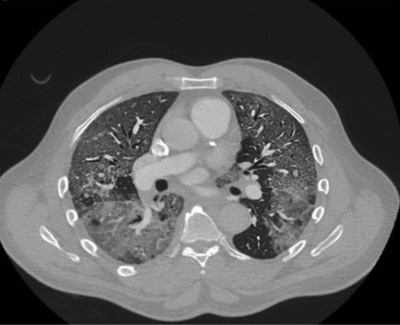

Well, if you fit the criteria based on age and smoking history, you're sent for what's called a low-dose CT scan. You're getting less radiation, which probably has some small benefit. And we’re looking for lung nodules. Lung nodules come in three flavors; solid, Ground Glass Opacities (GGO), and mixed nodules.

Solid nodules we worry about the most. You've got a two-centimeter solid lung nodule, something needs to be done. You need a diagnosis, biopsy, surgery. What we call GGO or Ground Glass Opacities are a little bit harder to deal with and still need to be followed. They can be potential lung cancers, but it’s less clear. And then there are these mixed nodules that are mostly ground-glass but have a solid component. Those are also concerning for developing lung cancer.